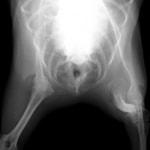

■ミニチュアダックスフント 1歳 去勢オス

前肢の成長板早期閉鎖、前肢の重度の外反変形が認められました。

関節面の変形が重度に認められます。